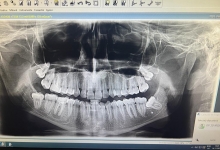

Clinica LUY ESTHETIC ART defineste parodontoza ca fiind rezultatul direct al placii dentare, care se depune pe suprafata dintilor, dar si in apropiere de marginea gingivala. Aceasta boala duce la pierderea dintilor, chiar daca ei sunt aparent sanatosi si nu prezinta carii. Edentatiile, afecteaza vorbirea, aspectul, dar si capacitatea de a mesteca.

Boala parodontala are un caracter progresiv. Pentru cazurile mai grave, recomandam tratamentul parodontal chirurgical rezectiv sau regenerativ.

Recomandam controale periodice (3-6 luni) pentru igienizari profesionale: detartraj, periaj dentar, air-flow etc. Aceste operatiuni asigura sanatatea gingiei, iar osul alveolar si ligamentele parodontale isi pastreaza integritatea.